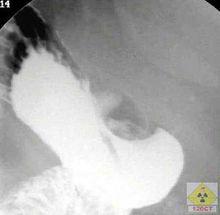

一、X線鋇餐檢查氣鋇雙重對比造影能更好地顯示黏膜象。潰瘍的X線徵象有直接和間接兩種:龕影是直接徵象,對潰瘍診斷有確診價值。良性潰瘍凸出於胃、十二指腸鋇劑輪廓之外,在其周圍常見一光滑環提,其外圍輻射狀黏膜皺襞。間接徵象包括局部壓痛、胃大彎側痙攣性切痕、十二指腸球部激惹和球部畸形等,間接徵象僅提示有潰瘍。